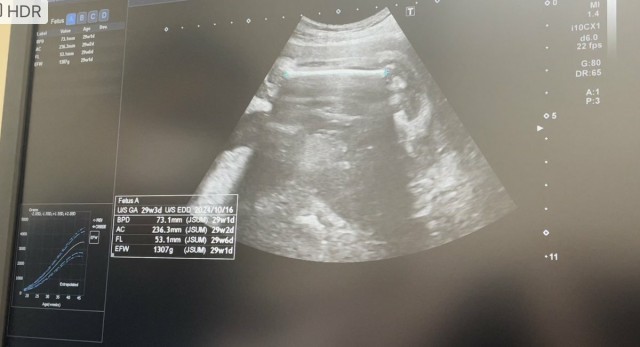

28週!妊婦健診 先週はコロナでダウンして体重も減ったからベビちゃんの成長心配だったけど順調に大きくなってた? もう妊娠後期だなんて早い、、、 すくすく育っておくれ